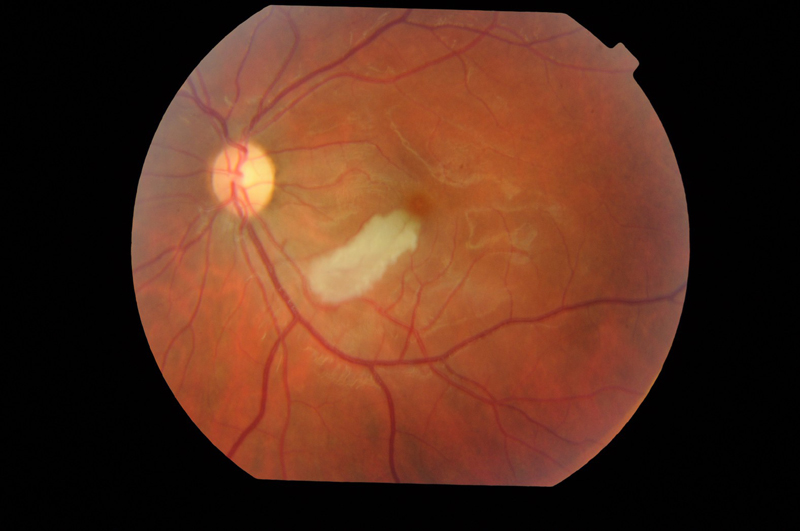

ORAR

Los pacientes con ORAR se quejan de disminución de AV monocular limitada a una zona del campo visual donde se encuentra la obstrucción. La fundoscopia revela edema retiniano en el territorio de la rama ocluida. Los émbolos pueden ser visibles hasta en el 66% de los casos

48,49 (

Figura 4 y

Figura 5).

Figura 4. Edema retiniano por oclusión de pequeña rama arterial temporal inferior en paciente con Síndrome de Susac.

Figura 5. Edema asociado a oclusión de rama arterial temporal inferior.